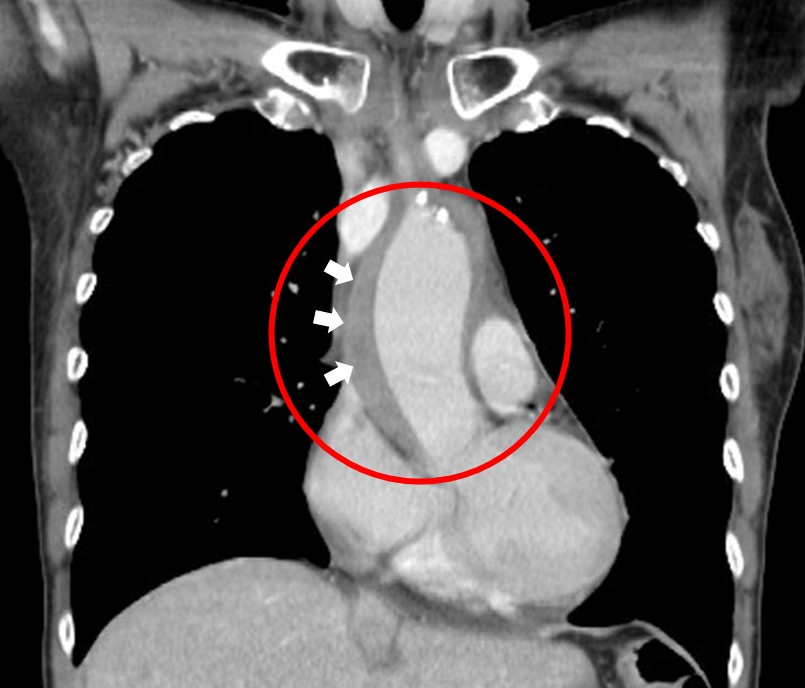

影像呈現升主動脈壁內血腫/圖:臺北慈濟醫院提供

平時工作壓力大、作息不規律的五十五歲王女士,疏於留意身體狀況,因持續三天前胸穿透後背的撕裂性胸痛,至台北慈濟醫院急診,檢查發現收縮壓高達210毫米汞柱,從胸部電腦斷層掃描看到升主動脈被一圈血塊包圍,最厚處約有1.5公分,但未發現明顯的剝離破口與夾層,診斷為「升主動脈壁內血腫」(Intramural hematoma,IMH);經藥物積極降壓後,追蹤血腫仍未改善,緊急進行升主動脈置換手術,術後兩周王女士康復出院,穩定門診追蹤,無任何後遺症。

徐展陽說,升主動脈剝離病患中約有10%到20%的表現為非典型主動脈剝離,如升主動脈壁內血腫,成因是血管外壁的小血管破裂,在升主動脈外圍形成血腫包圍。